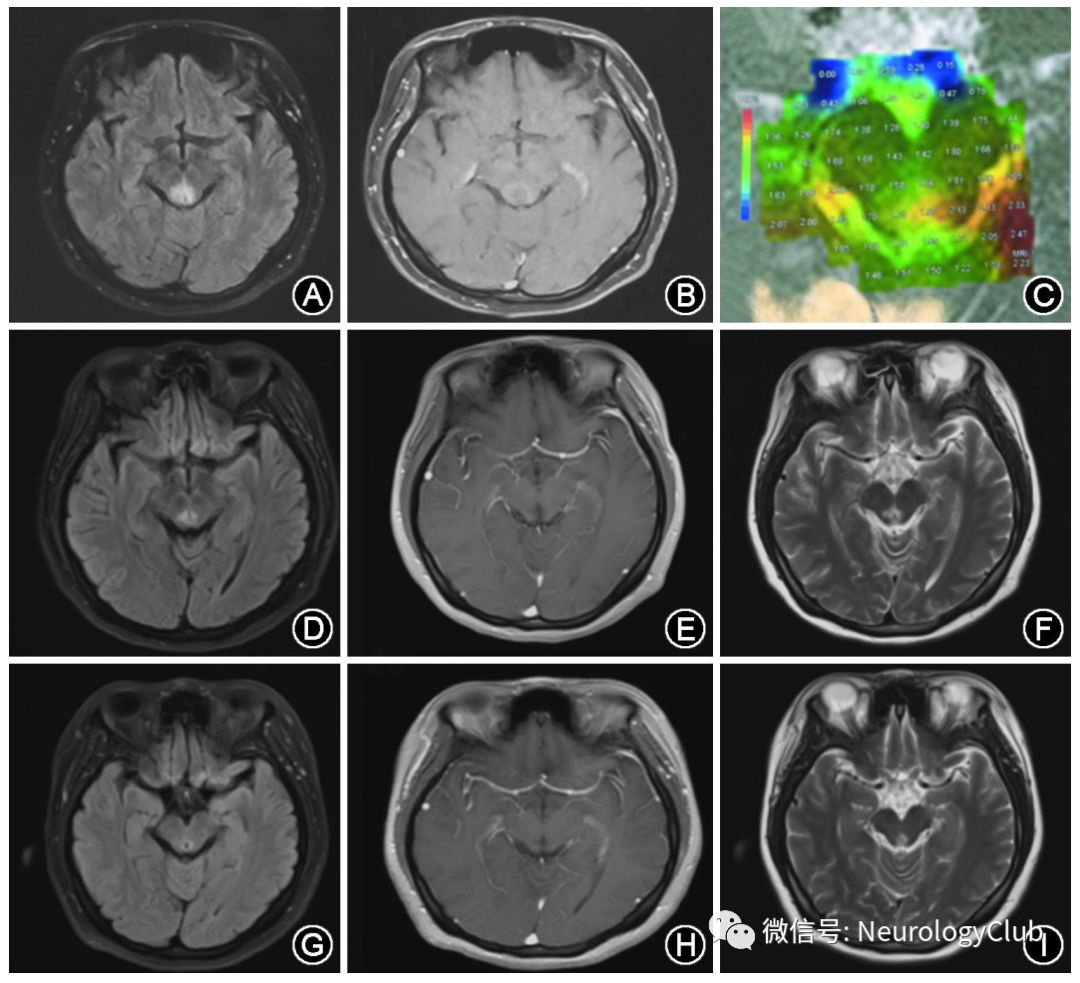

(图1:患者影像学检查;A-C为2016年9月1日于外院检查;A:头MRI平扫T2FLARI像;B:头MRI增强;C:头MRS;D-F为2016年10月13日于天津市环湖医院检查;D:头MRI平扫T2FLAIR像;E:头MRI增强;F:头MRI平扫T2像;G-I为2017年3月9日于天津市环湖医院检查;G:头MRI平扫T2FLAIR像,H:头MRI平扫增强;I:头MRI平扫T2像)

脑脊液抗NMDAR抗体(++),血清抗NMDAR抗体(-)。考虑诊断抗NMDAR脑炎,予人免疫球蛋白400mg/kg每日一次静脉点滴(5d)及甲泼尼龙500mg每日一次静脉点滴(5d)冲击治疗,随后甲泼尼龙240mg每日一次静脉点滴(3d),120mg每日一次静脉点滴(3d),后改为泼尼松60mg每日一次口服,逐渐减量至半年后停药。患者视物成双症状明显好转,仍有多睡、睡眠异常症状。2016年10月随诊复查,肝肾功能、电解质、心肌酶、血脂血糖、血尿便常规、凝血功能等均正常范围,复查头MRI平扫+增强(2016年10月13日)示中脑异常信号,未见明显强化(图1)。于2017年3月随诊复查:头MRI平扫+增强(2017年3月9日)示较前次检查(2016年10月13日)无明显变化(图1)。行腰穿复查脑脊液常规、生化、免疫、病理均正常范围,化验脑脊液NMDAR抗体(-);血NMDAR抗体(-)。动态脑电图提示:清醒脑电:以10/s左右的α节律为主,电压正常范围,分布以双侧顶枕为著,双侧基本对称,调节调幅欠佳;前头部导联散在出现少量快波活动;未见阵发性异常及痫样波发放。睡眠脑电提示:对称顶尖波、对称纺锤波。睡眠监测回报:(1)平均睡眠潜伏期明显缩短(正常>10min,<5min具病理意义);(2)可见2次SOPEMPs(≥2次具病理意义),考虑发作性睡病可能性大。神经心理量表评分:简易智力状态检查量表(MMSE)30分,蒙特利尔认知评估量表(MoCA)30分,汉密尔顿(Hamilton)抑郁量表1分(害怕拖累别人),抑郁自评量表(SDS)29分,焦虑自评量表(SAS)31分,汉密尔顿(Hamilton)焦虑量表4分(焦虑心境、害怕一人独处、注意力不集中、抑郁心境),精神神经量表(NPI)患者评估分级10分(幻觉,表现为睡前自觉身上有东西爬,频度:经常,程度:轻度;睡眠/夜间行为,表现为白天睡眠过多,频度:非常频繁,程度:轻度);护理者苦恼分级1分。

本病例患者头MRI表现为局灶性的中脑背侧导水管周围异常信号,边缘轻度强化,经免疫治疗1个月后,头MRI病灶信号未再强化,脑脊液抗NMDAR抗体转阴。但患者为年轻女性,突发中枢神经系统局灶性症状,影像学表现为脑干病变,脑脊液寡克隆带阴性,是否并发多发性硬化或孤立综合征,尚需长期随访。同时患者还存在多种系统性自身免疫性疾病相关抗体,是否为混合性结缔组织病也需进一步观察随访。